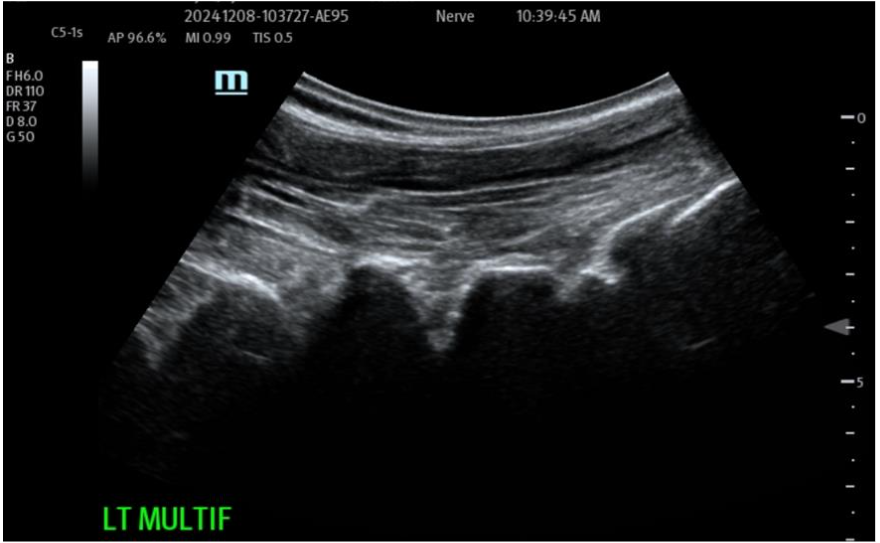

Figure 2: Use of sterile field Ultrasonographic Imaging for diagnostic and therapeutic Targeting of supportive structures Tissue Remodeling: The Biocellular contributions, with the synergy provided, between the addition of blood-derivatives (growth factors and cytokines/chemokines) and the stem/stromal complex, with its ECM scaffolding interact WITH the damaged or degenerative sites directly. This facilitates the repair of tissues in concert with the local existing microenvironments to help remodel and regenerate damaged, aging and degenerative structures. This impact is potentially seen to be helping slow down, or reverse, damaged/degenerative processes and assisting the needed healing processes per se. This is a result of both inflammatory modulation, immune protection and revascularization + perfusion improvements. More detail is beyond the scope of this Chapter, but is available in the peer-reviewed literature.

Figure 3A: Pre-operative treatment site Multifidus (loss of function dynamically) at L4-5 and above. Multiple targets IM for return of function and architecture. NOTE: Likely most common site that accompanies Lumbar facets pain seen together and is treated. Figure 3B: Post-Biocellular treatment (18 mon.) Piriformus Syndrome.